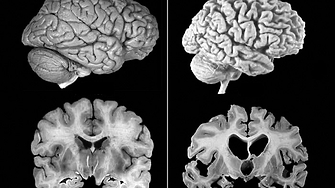

Дългогодишните изследвания за намиране на лекарство срещу Алцхаймер са пред

...... сериозен ефект при лечението.Според прогнозите на СЗО до 2050 година пациентите с Алцхаймер ще се увеличат до 139 милиона, ако не се появи ефективно лечение.